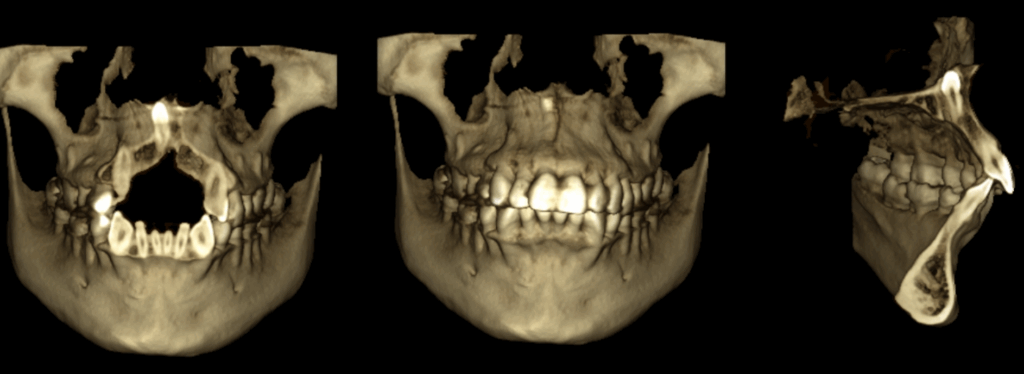

En las reconstrucciones 3D se representa de manera didáctica Mesiodent en posición invertida (Figura 4).

RECONSTRUCCIÓN 3D

- Mesiodent en posición invertida